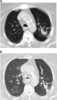

Cavitating pneumonia

Pneumonia is an inflammatory condition of the lung primarily affecting the small air sacs known as alveoli. Symptoms typically include some combination of productive or dry cough, chest pain, fever and difficulty breathing. [Source: Wikipedia ]